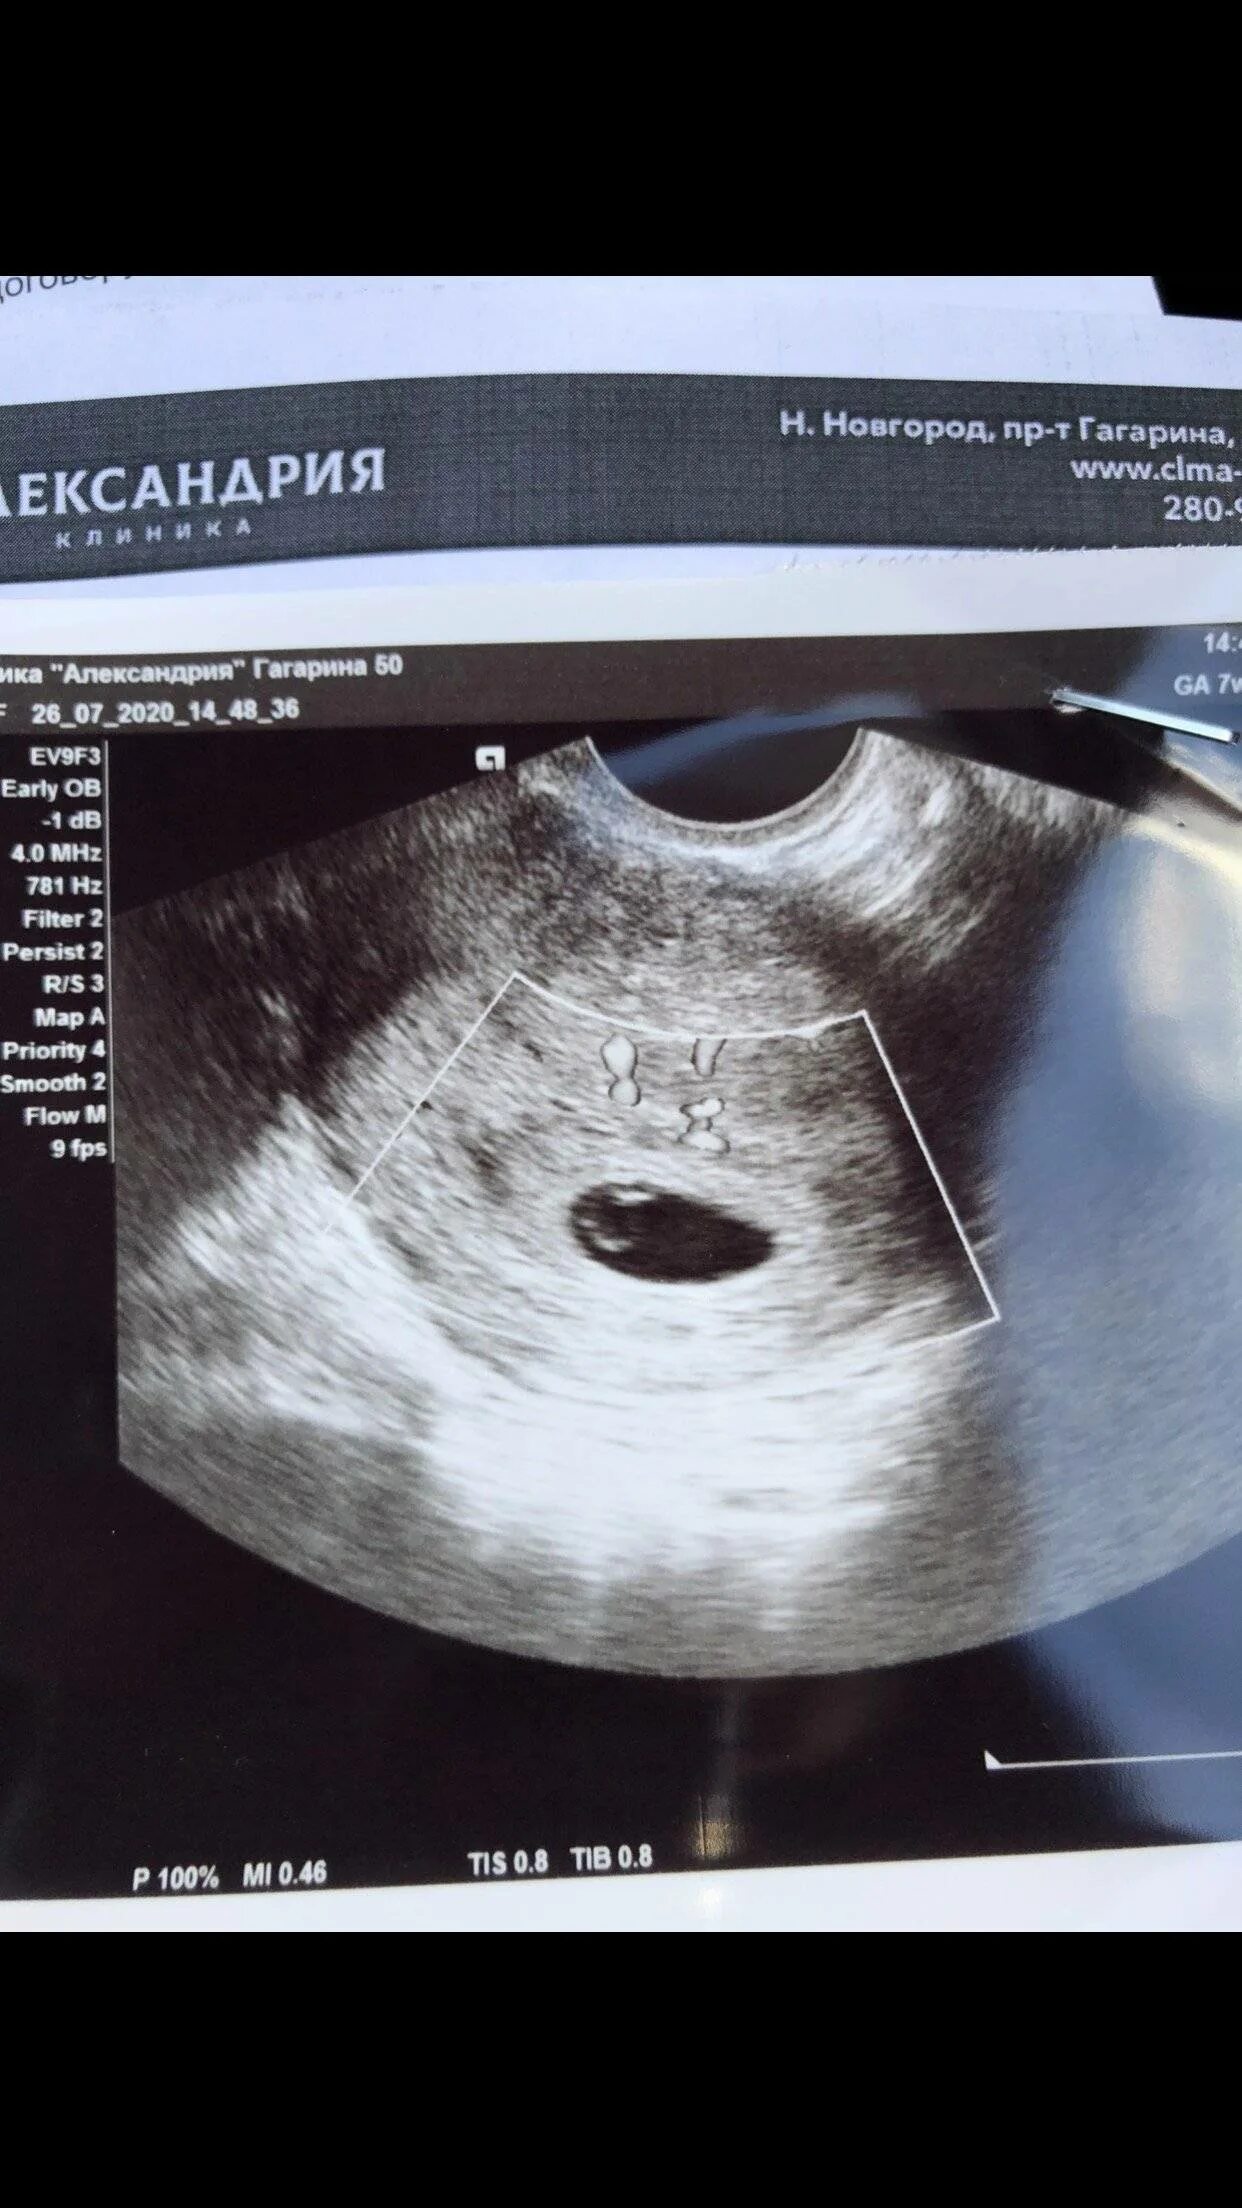

Можно ли в 6 недель